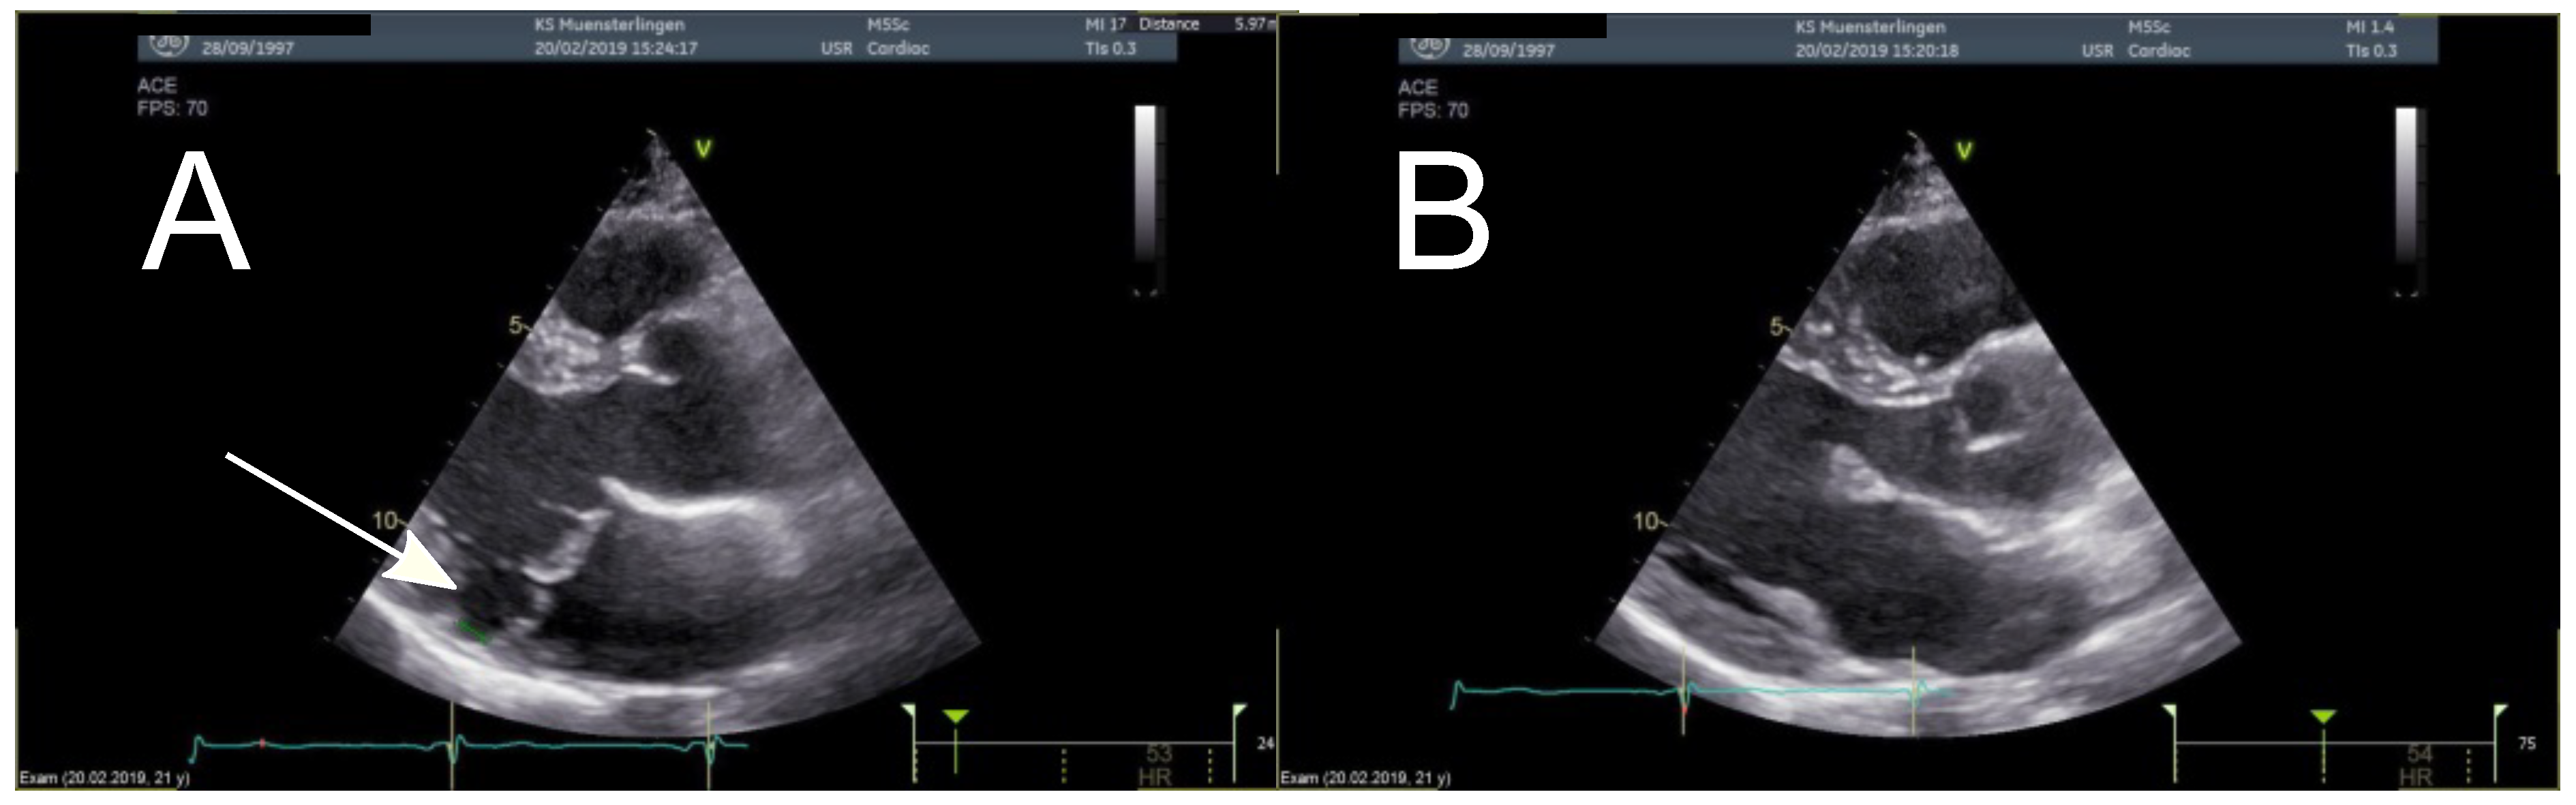

- Muthukumar, L.; Rahman, F.; Jan, M.F.; Shaikh, A.; Kalvin, L.; Dhala, A.; Jahangir, A.; Tajik, A.J. The pickelhaube sign: Novel echocardiographic risk marker for malignant mitral valve prolapse syndrome. JACC Cardiovasc. Imaging 2017, 10, 1078–1080. [Google Scholar] [CrossRef] [PubMed]